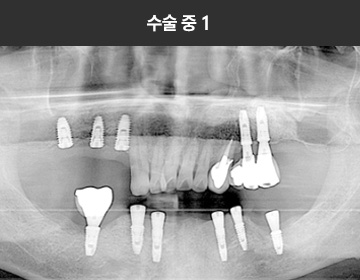

BMP를 이용한 수술 사례      I

치료 기간 : 2023.03.22 ~ 2023.09.15

* 상기 사례의 경우, 해당 의료기관에서 진료를 한 환자분의 동의를 얻어 사용되었습니다. * 치료 전후의 사진은 동일 인물과 동일한 조건에서 촬영 되었음을 알려드립니다.

* 모든 수술 및 시술은 개인에 따라 부작용고지 : 임플란트치료는 치료 후 감염,

염증, 연조직합병증, 출혈, 감각이상 등의 부작용이 있을 수 있습니다.

의료진과 충분히 상의 후 신중하게 결정하시기를 바라겠습니다.